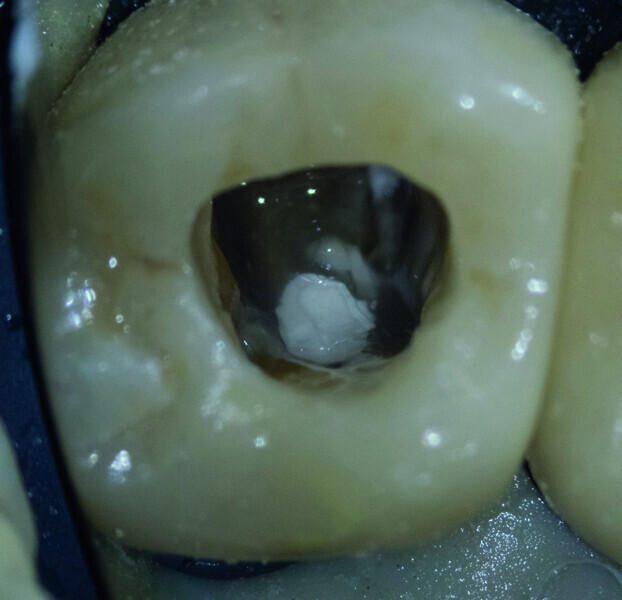

Fig. 3 : La perforation a été fermée avec un ciment hydraulique à base de silice.

Fig. 4 : L’orifice a été provisoirement fermé avec un matériau d’obturation hygroscopique provisoire et recouvert d’un composite fluide de couleur bleue.